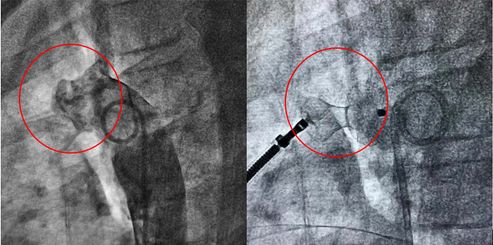

左图:主动脉造影可见主动脉和肺动脉间异常通道

右图:封堵器准确释放后PDA封闭

患者是一名10岁儿童,因准备做耳鼻喉手术住院,术前准备过程中发现心脏杂音。通过超声心动图发现该儿童存在6mm动脉导管未闭(PDA)。长期动脉导管未闭导致大量持续性左向右分流,最终将导致肺动脉高压、心力衰竭等,甚至可能发生右向左分流、艾森曼格综合征,从而丧失手术机会死亡。及时闭合动脉导管,刻不容缓!心脏内科电生理团队在李学斌教授的指导下,经过周密的术前准备,儿科精心配合,优化手术流程,成功完成了PDA封堵术,以微创的手术治疗方式,使得困扰小朋友10年的先天性心脏病得到治愈。